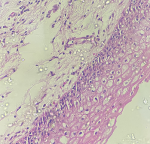

Of the 140 patients, 38 were diagnosed with mild ectocervical dysplasia. The mean AI increased progressively from the lower to the higher grades of CIN. Apoptotic index significantly increases from CIN 3 to carcinomas. Cell counts also increased notably from CIN I to CIN II and III. A sharp increase in AI from CIN 3 to the carcinoma cervix may suggest potential genetic alterations in CIN3 cells, which could drive the malignant transformation from CIN3 to cervical cancer [1,2]. The flaw in the apoptotic pathway enables cells to multiply despite the presence of genetic mutations. Therefore, AI can be used to evaluate the importance of apoptosis as an indicator of proliferation [3]. Mean AI was calculated using descriptive statistics. Of these, 53 cases had squamous metaplasia, 38 had mild dysplasia (Figure 1), 19 had moderate dysplasia (Figure 2), and 14 had severe dysplasia (Figure 3), 16 cases of malignancy (Figure 4) were evaluated (Table 1). In squamous metaplasia (Figure 5), the mean AI was 1.03, while in mild cervical dysplasia it was 1.51. For moderate cervical dysplasia, the mean AI was 3.06, and for severe dysplasia, the mean AI was 5.23. In cases with overtly malignant cervical lesions, the mean AI was 7.35. The mean AI showed a progressive increase with higher dysplasia grades. The most common age groups for squamous metaplasia (19 cases), mild dysplasia (17 cases), and moderate dysplasia (7 cases) were between 35 and 44 years, whereas for severe dysplasia (5 cases), it was between 55 and 64 years. The most common age group for malignancy (9 cases) was 45-54 years (Table 1). The Ki-67 proliferation index in malignant cases ranged from 70% to 80% (Figure 6), whereas in non-malignant cervical lesions, it was between 1% and 2% (Figure 7). Squamous metaplasia, mild dysplasia, moderate dysplasia, severe dysplasia, and malignancy all showed significant, p-values (Table 2). To confirm findings of dysplasia in mild and malignant tumors, Ki-67 staining was performed. Ki-67 expression correlated with the apoptotic index (Table 3). A higher AI is indicative of high-grade epithelial dysplasia. AI can be utilized as a prognostic marker for the follow-up and monitoring of patients with epithelial dysplasia. AI serves as both a diagnosis and prognosis marker in patients with epithelial dysplasia.

Figure 2: H&E; x 100, moderate dysplasia in ectocervix